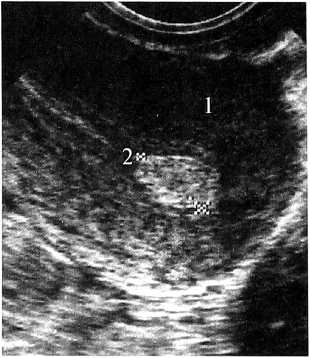

Всем 120 пациенткам с ЛУГ в эндометрии (рис. 6) была назначена КГТ (бромокриптин,жанин, мерсилон, дюфастон, норколут). Через 3—6 месяцев после проведения КГТ при нормализации гормонального фона — у всех обследованных в эндометрии не определялись ЛУГ; эндометрий был однородным.

Рис. 6а. Рис. 6б.

Рис. 6. Та же больная. 11 день МЦ, через три месяца после приема КЭТ (бромокриптин).

Эндометрий соответствует пролиферативной фазе, без влияния секреторной фазы. Продольное ТВ-сканирование: 1 — матка, 2 — М-эхо без ЛУГ; а) — до введения окситоцина; б) — после введения окситоцина образования при ДН, отсутствие изменения формы и размера при ФФДП.